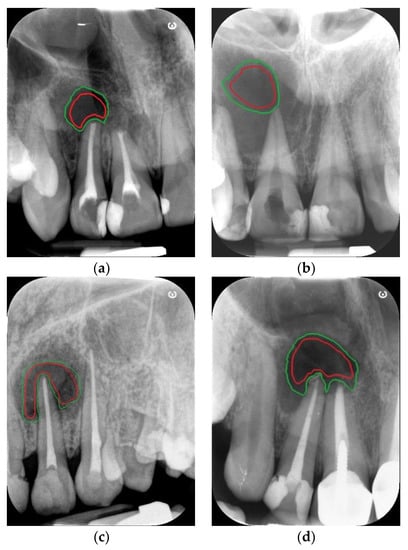

The documentation covered images of 62 patients of both sexes aged 34–61 years with histological evaluation in the diagnostic process. Periapical radiographs were obtained using a dental X-ray system (Gendex Kavo 765 DC Intraoral X-Ray System, Biberach, Deutschland). Data were acquired at 65 kV and 7 mA with a mean exposure time of 0.1 s and recorded on phosphor plates with a secondary readout of five detectors (CS 7600, Carestream Dental LLC, Atlanta, GA, USA) connected to a Kamsoft computer system. The resolution of the image varied from min. 490 × 649 to max. 1528 × 2024 pixels depending on the recorded details. There were 23 samples presenting granulomas and 39 presenting cysts. For each lytic lesion, two ROIs were manually annotated on each image, the first containing the maximum area of the lesion interior and the second containing an extension of this area to include the edge of the lesion (Figure 2).

Figure 2.

Example of ROI outlines: for granulomas (a,c), for cysts (b,d). Legend: red for the lesion interior outline, green for the outline including the lesion edges.